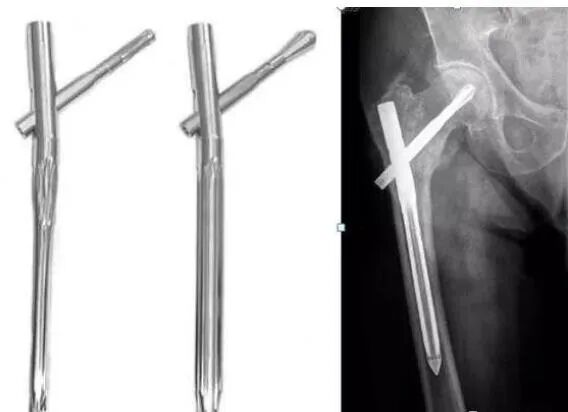

胫骨干、股骨干、肱骨干等部位的骨折经常会使用髓内钉技术。有时候髓内钉还挺难取的,而且钉子在骨头内部也不影响啥,可取可不取。

术前要了解所使用髓内钉的类型和厂家,保证打拔器与髓内钉尾端配套; 一般先取锁钉,最后留一枚锁钉拧松后放在原位,以免全部锁钉取出后,安装打拔器时主钉掉入髓腔;待打拔器安装牢固后取出最后一枚已经拧松了的锁钉;(Gamma钉、PFN等可留一枚拉力钉再安装打拔器)

术中若遇到髓内钉卡压过紧的情况,在保证打拔器与髓内钉良好连接的前提下可先用适中力量将髓内钉往里敲打,然后再往外拔,反复几次即可拔出; 如髓内钉拔出特别困难,要注意检查锁钉是否已全部取出;

图2 使用内六角起子取出钉帽为内六星形的螺钉。(由左而右)A.内六星形钉帽与内六钉帽示意图;B.内六起子可卡入星形钉帽;C.内六起子取出内六星形锁定钉图3 有联合孔的锁定钢板,螺钉和钢板出现“冷焊接”时可通过相邻孔钻洞后整体撬出。(由左而右)A.锁定钉相邻孔钻洞:B.敲击钢板,使钢板螺钉整体移动;C.螺钉滑人洞中、撬出。注:图片来源于文献[4] 图4 胫骨髓内钉尾帽卡死时的取出方法。(由左而右)A.暴露髓内钉近端锁钉孔;B.克氏针一端制作成钩,钩住近端锁钉孔拔出

图5 胫骨髓内钉尾和滑动锤连杆不匹配时的取出方法。(由左而右)A.用克氏针制作倒钩;B.穿入髓内钉尾帽;C.重新安装尾帽;D.克氏针另一端连接滑动锤。